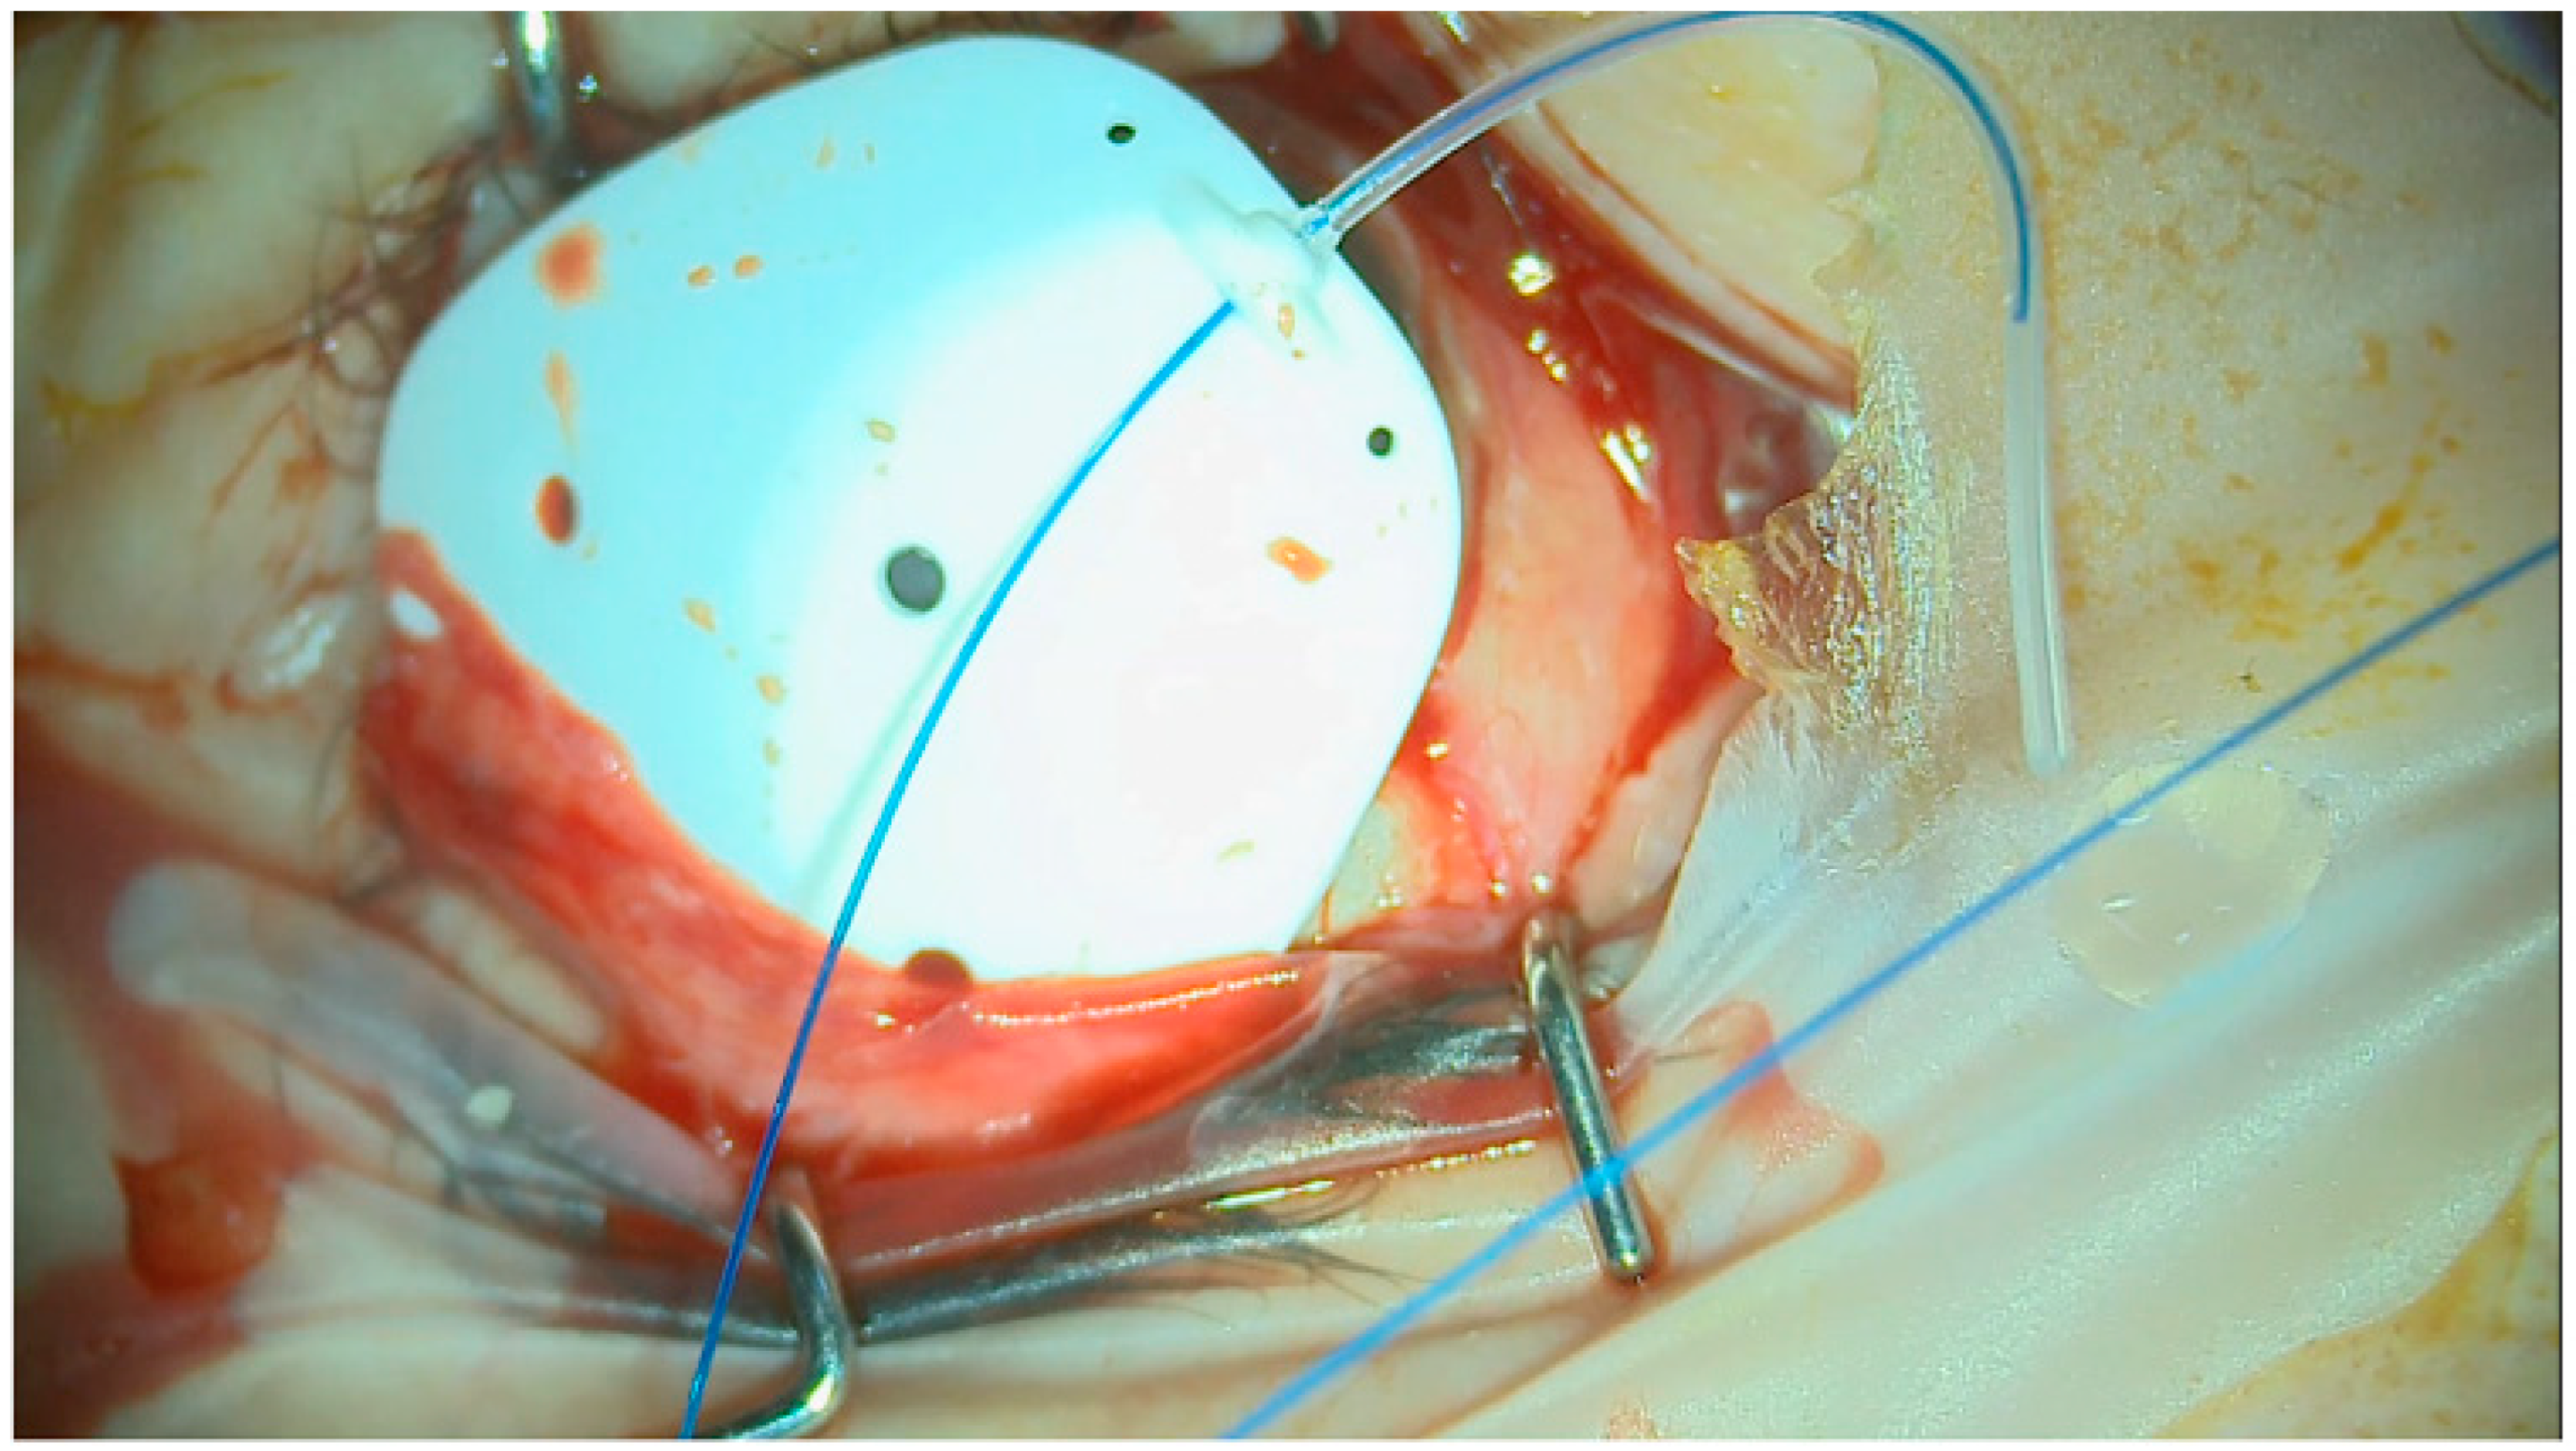

Prior to the attachment of the plate to the sclera, a 3/0 prolene suture was fed into the tube to occlude it (Figure 3). There was no need to hook the recti muscles for this technique. The eyePlate-300 was placed into the superior-temporal quadrant between the superior and lateral recti 10 mm from the limbus and sutured via the two anterior fixation holes on the plate to the sclera with 9/0 prolene.

Figure 3. Intraoperative view of eyePlate-300 by Rheon Medical with 3/0 prolene stent inserted.